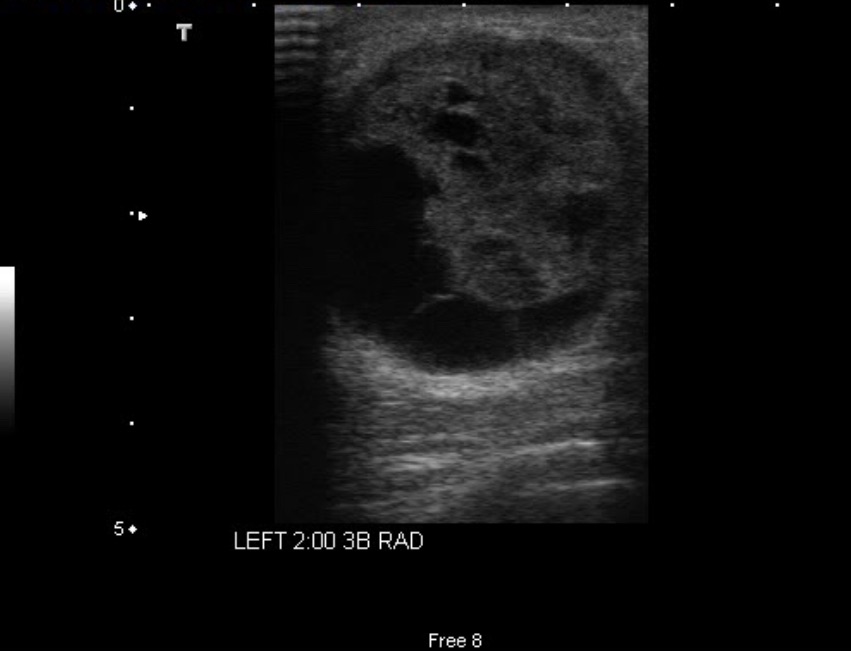

- The ultrasound shows a round lesion that is neither elliptical nor gently lobulated, so even if a thin echogenic capsule could be identified, none of the 3 defined benign criteria are met:

- When there is a thin echogenic capsule in a solid lesion that does not meet the other criteria:

- There is a 14% chance of malignancy:

- Therefore, further evaluation is necessary

- Although the lesion shown above would be considered BIRADS 3 by many radiologists, and 6-month follow-up would perhaps be recommended, that approach might cause unnecessary anxiety:

- There would also be the possibility of diagnostic delay if the lesion turned out to be a well-circumscribed cancer

- For these reasons, the best approach is to aspirate the lesion and try to evacuate the fluid:

- Sometimes the “fluid” is the consistency of toothpaste and requires a 16- or even 14-gauge needle to evacuate it:

- If nothing is obtained with a large bore needle, core needle biopsy is indicated